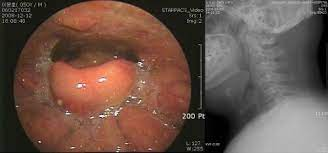

이처럼 후두개염은 고열과 인후통, 목소리 변화 등의 증상이 나타나는데

악화되면 위의 자료와 같이 기도가 막히면서 호흡 곤란, 기도 폐쇄가 나타날 수 있습니다.